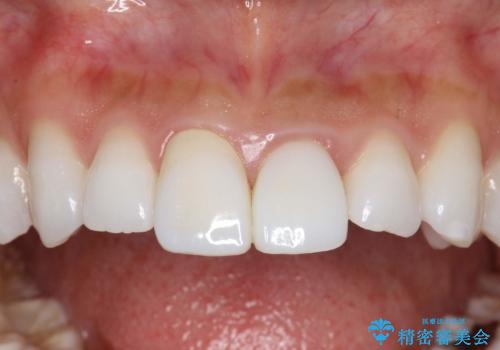

【歯周外科】審美的に気になる短い前歯の長さを歯茎の外科手術とセラミックで揃える

左上の前歯がわずかに短いことを気にされていたため、歯周外科にてこれを可及的に改善し、セラミックにて修復を行いました。

セラミックの種類:PFZ standard